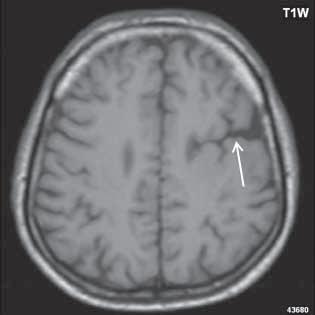

Obr. I.1.1c Fyziologické změny v závislosti na věku baze lební a corpus callosum, hypersignál v přední části kosti klínové (žlutá kostní dřeň) ve 2 roce života (šipka)

Obr. I.1.1d Fyziologické změny v závislosti na věku baze lební a corpus callosum, zvýšený signál v oblasti celé kosti klínové a klivu (žlutá kostní dřeň) (šipka), dochází k pneumatizaci a vývoji sinus sfenoidalis (přerušovaná šipka) ve 4 roce života